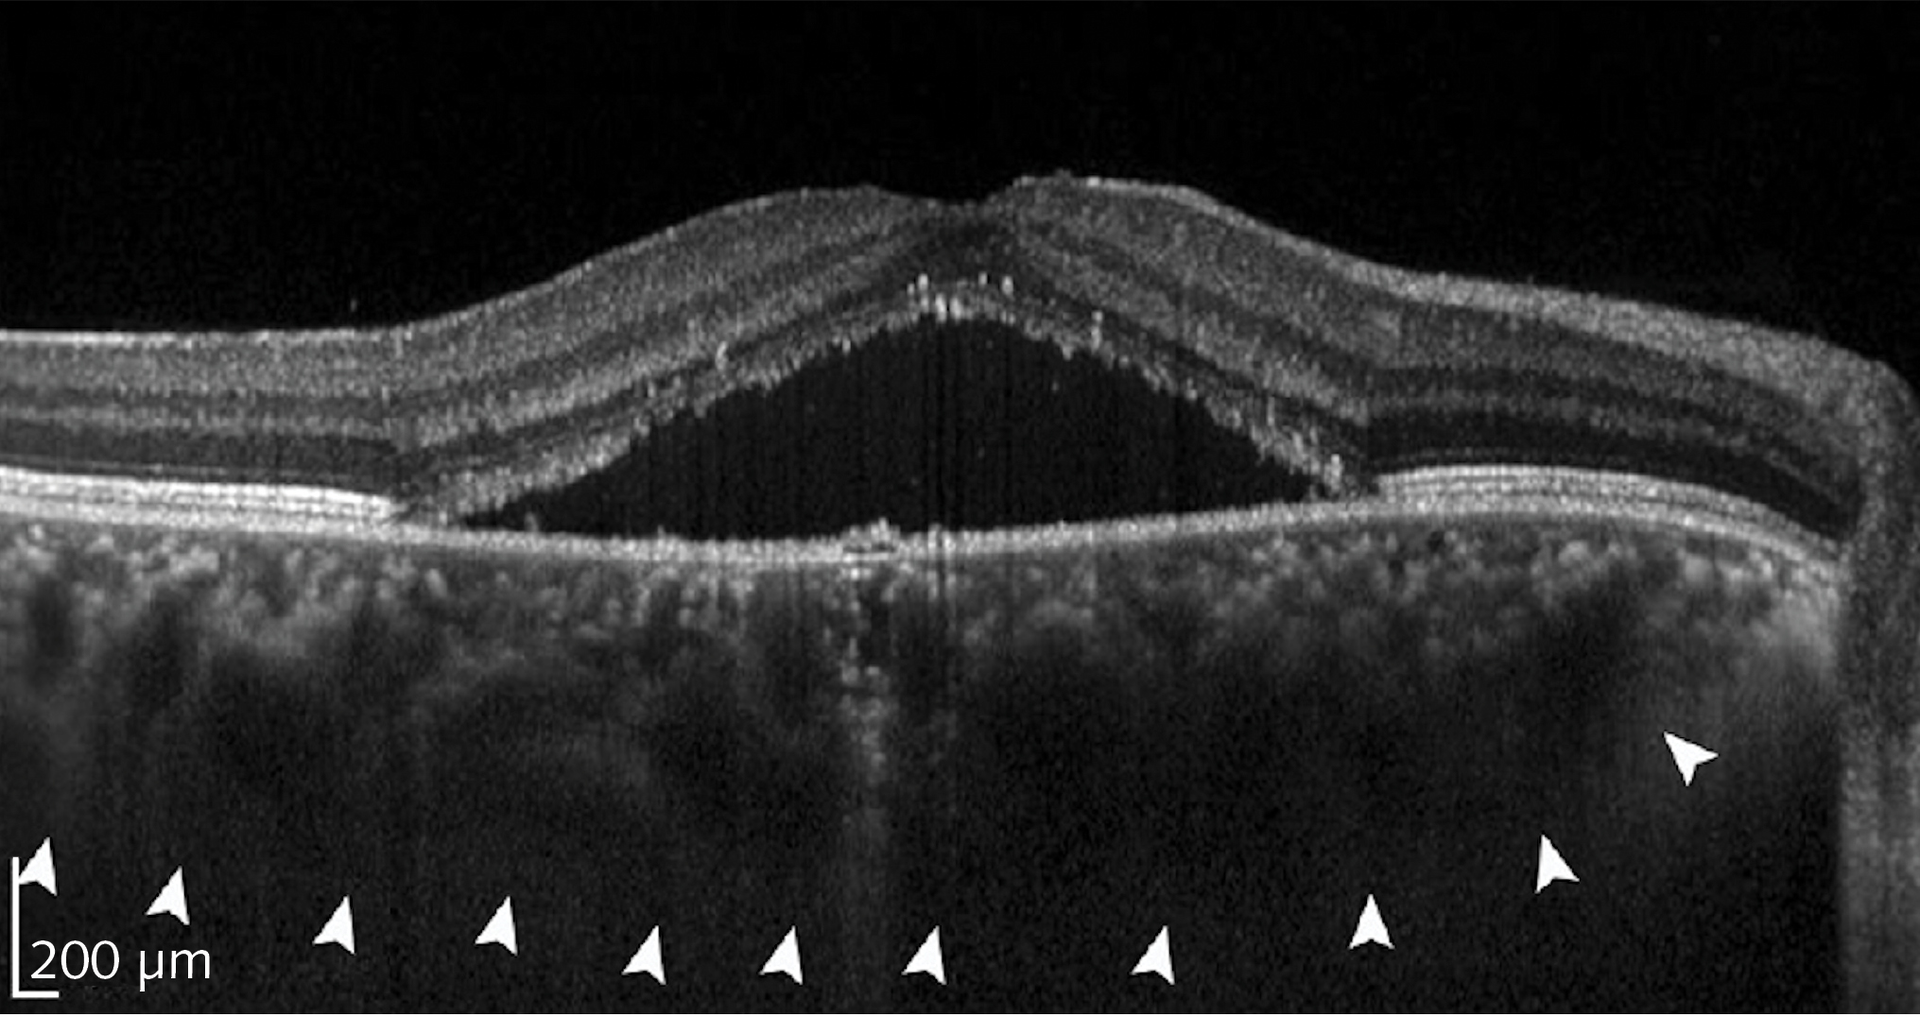

Sina Farsiu, director of the Vision and Image Processing Laboratory at Duke University (Durham, NC), leads a team looking to optimize treatment of diabetic retinopathy (DR). Advanced DR blocks existing retinal blood vessels and triggers formation of new ones. The current standard of care is to treat every patient with antivascular endothelial growth factor (anti-VEGF) drugs, and then see if the patient responds. Many DR patients will not, and that, the team notes, is “costly and burdensome for both patients and physicians.” Farsiu’s goal was to classify responsive and unresponsive patients by analyzing a single pre-treatment OCT image set.

They collected a database of images from 127 patients, all with diabetic macular edema, which is fluid leakage that thickens the retina and degrades vision. All patients were treated with one of the standard anti-VEGF drugs at four- to six-week intervals. After three treatments, OCT images were again acquired, reflecting the clinical practice of evaluating patients’ response at that time. Members of the study group were classified as “responsive” if the retinal thickness decreased by at least 10%, and “nonresponsive” otherwise. Eighty of the patients were responsive and 47 nonresponsive, consistent with percentages in the general population.

Farsiu’s team created a CNN architecture with six “attention blocks,” which are essentially elements that allow the network to weight “interesting” image areas more heavily. They compared the CNN performance against that of several popular learning architectures. Their architecture significantly outperformed the alternatives, with 87% precision and 85% specificity. Performance for very responsive and very unresponsive patients was even better. The team concluded that “the ability to accurately select highly responsive and very poorly responsive patients prior to treatment would be beneficial for practicing physicians and potentially for subject selection in clinical trials of novel therapies for DME.”